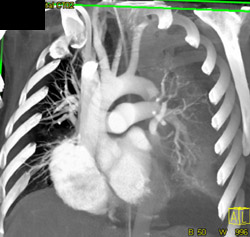

Hydropneumothorax